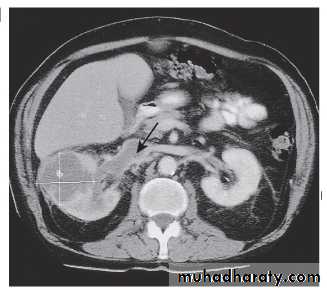

The initial investigation is ultrasound, which allows differentiation between solid tumour and simple renal cysts. Thereafter, a contrast-enhanced CT of the abdomen and chest should be performed for staging .Management and prognosis